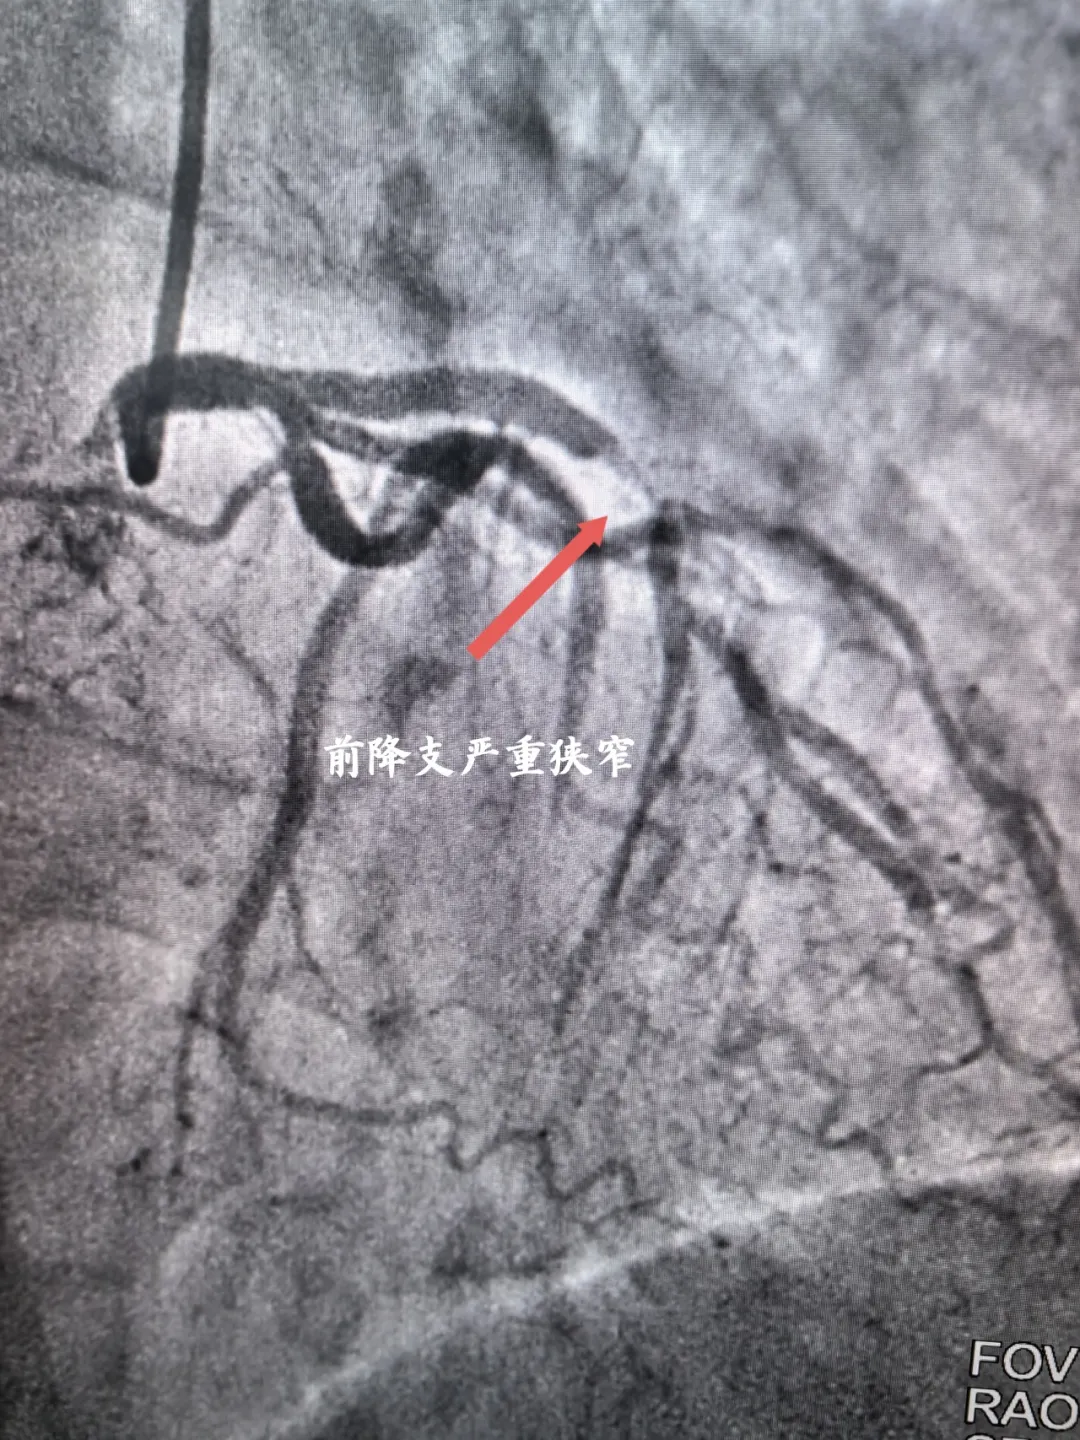

入院完善各項檢查后考慮為冠心病合并右鎖骨下動脈狹窄可能,經(jīng)宋坤青主任團隊研究后,決定為該患者施行冠脈造影+鎖骨下動脈造影。經(jīng)過嚴謹?shù)男g(shù)前討論及充分的術(shù)前準備后,在2024年06月07日上午,宋坤青主任、趙博韜副主任及楊亞楠、冉德聰主治醫(yī)師為該患者進行了造影手術(shù),結(jié)果提示右冠狀動脈近近段90%狹窄,前降支近中段90%狹窄,右側(cè)鎖骨下動脈閉塞。

前降支嚴重狹窄